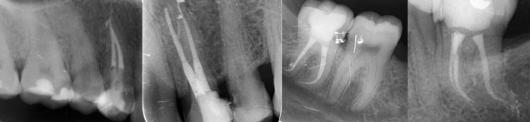

Poza Endodontie

Endodontia este ramura stomatologiei care se ocupă cu tratamentul partii dintelui (radacina) care nu este vizibila in cavitatea bucala. Tratamentul de endodontie al unui dinte este o etapa din cadrul unui intreg proces, al carui scop este salvarea si pastrarea dintelui in cavitatea bucala. Este bine de stiut ca fiecare dinte prezinta o anatomie specifica. Pot avea 1-3 radacini si 1-4 canale. Molarii de minte intotdeauna sunt atipici; nu se stie cate canale poate avea sau daca sunt operabile in totalitate. Foarte rar se poate aplica tratamentul endodontic molarilor de minte. Teoretic ei sunt ”neendodontici”.

De ce la noi

Succesul unui tratament de endodontie consta in dezinfectia foarte riguroasa a canalelor dintelui si obturarea acestora in mod tridimensional, lucru pe care echipa noastra il efectueaza cu atentie si rabdare. Un alt aspect caruia trebuie sa i se acorde un interes deosebit, pentru ca tratamentul de endodontie sa aiba cele mai bune rezultate, vizibile in timp, este tipul de materiale utilizate. De aceea, folosim materiale 100% biologice, care nu dau coloratii in timp dintelui, pe care le combinam cu cele mai bune tehnici moderne in prepararea canalului. Alaturi de acestea, ne recomanda si sistemul pe care il utilizam in obturarea canalelor, si anume sistemul de obturare tridimensional, recunoscut pentru faptul ca realizeaza o sigilare mai eficienta, in comparatie cu sistemele clasice.